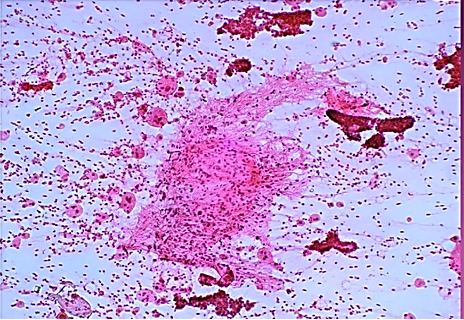

Figs 1 and 2 from a mass in the right hypochondriac region.

Make your diagnosis.

Fig 1 : Giemsa x 100

Fig 2 : Giemsa x 400